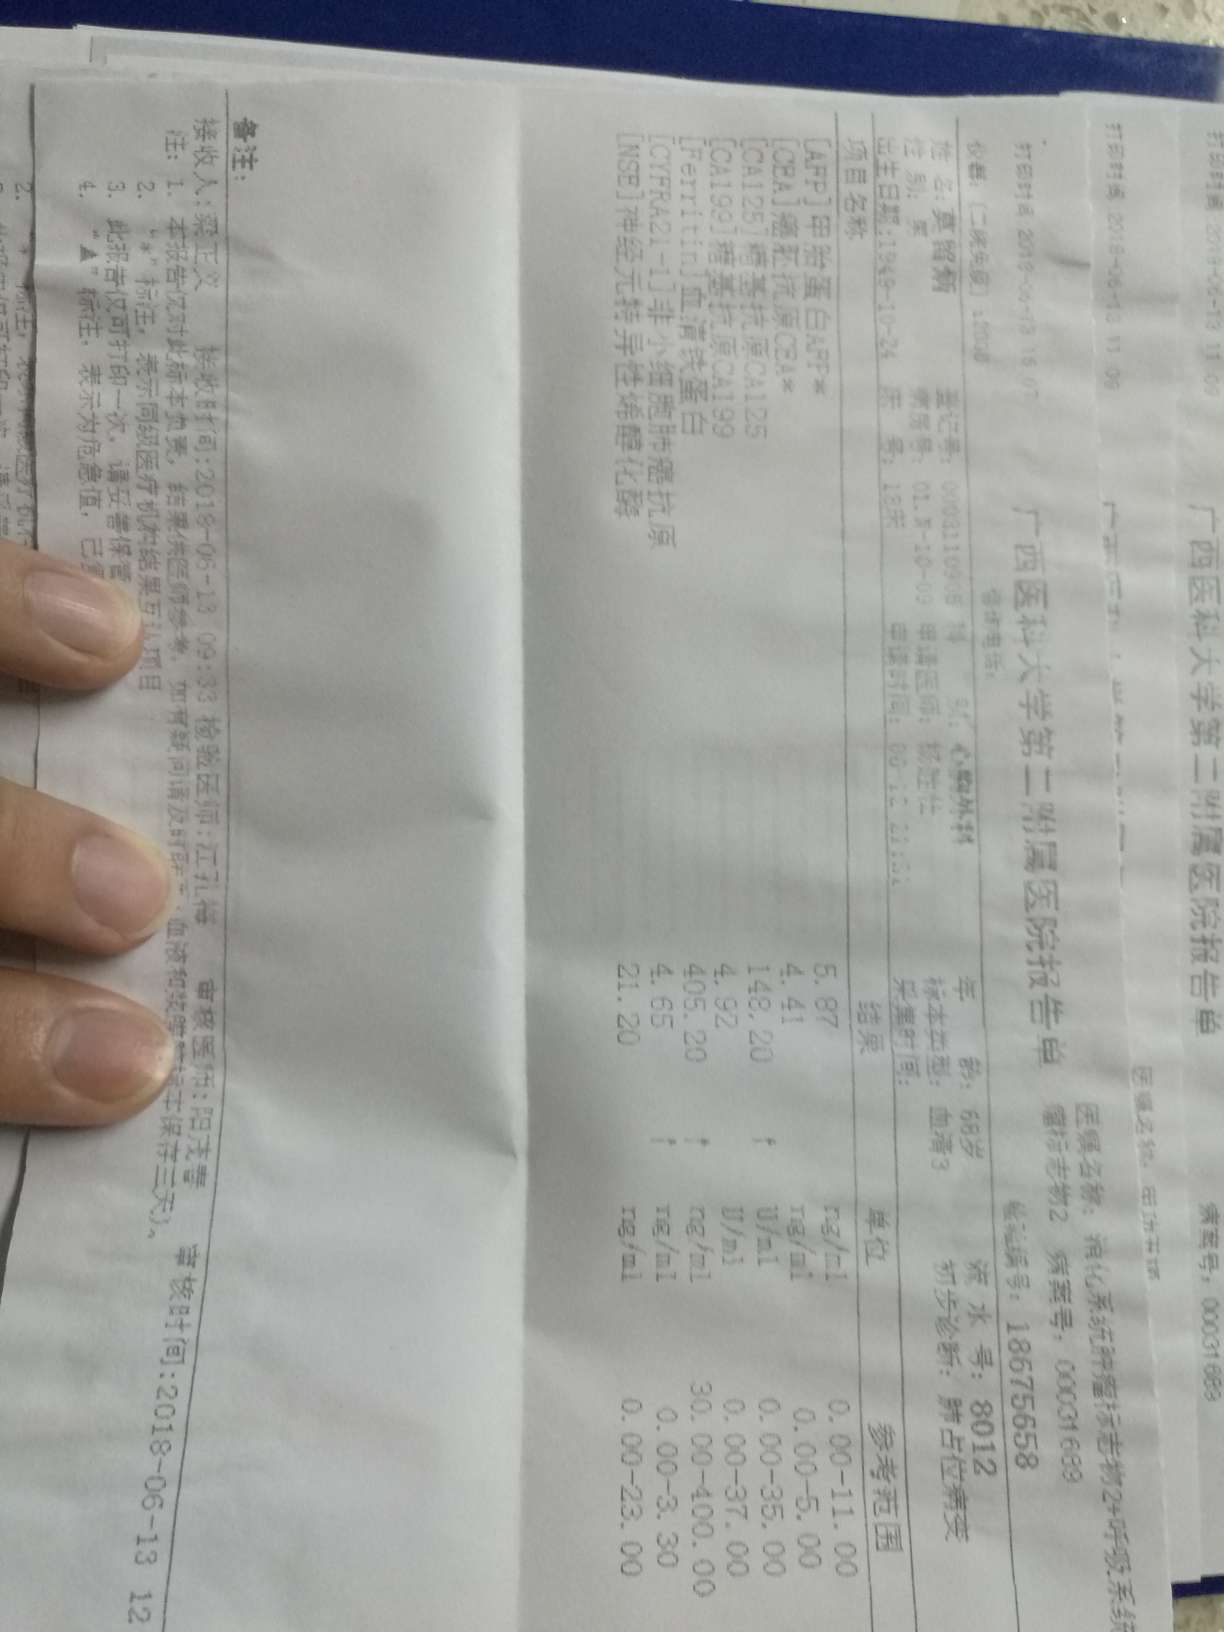

肝部阴影多了很多,骨转,肾上腺都有,同时疑似有脑转,肿瘤标志物数值也升幅很大

肝部阴影多了很多,骨转,肾上腺都有,同时疑似有脑转,肿瘤标志物数值也升幅很大